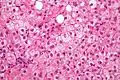

Ballooned cells are typically two to three times the size of adjacent hepatocytes and are characterized by a wispy cleared cytoplasm on H&E stained sections. They can be differentiated from adipocyte-like cells by their cytoplasm and nucleus; ballooned cells have their nucleus in the centre (unlike adipocyte-like cells, which have it peripherally). Also, ballooned cells have (small) pyknotic nuclei or nuclei that are undergoing karyorrhexis, i.e. in the process of disintegrating. The cytoplasm of cells undergoing ballooning degeneration is wispy/cobweb-like, while adipocyte-like cells have a clear cytoplasm or a vacuolated one.

Ballooning degeneration. H&E stain.